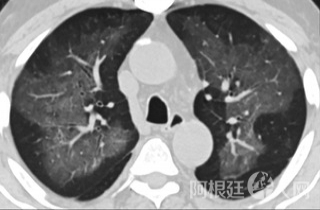

疑点一,电子烟患者的CT影像和临床表现并不具有特异性。所谓美国电子肺炎患者,其实是对没有其他合理诊断证据、吸食电子烟肺炎患者的统称。这些患者在病发前90天内吸食了电子烟,尤其值得注意的是,部分患者的CT影像特征和临床表现与病毒性肺炎患者极其相似。

中、下肺轴位CT平扫显示毛玻璃样混浊伴胸膜下保留。(同一病人CT影像)

中、下肺轴位CT平扫显示毛玻璃样混浊伴胸膜下保留(箭头)。(同一病人CT影像)